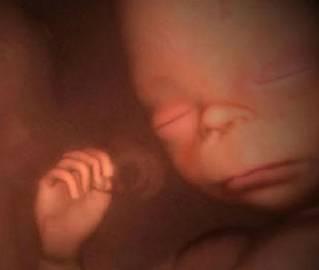

这部纪录片就是利用四维彩超技术检查宝宝的情况并且通过计算机生成图像,可以清楚的看出宝宝生长发育的过程,甚至可以观察到宝宝的每一次胎动,每一个眨眼和微笑。

第二张图片中双胞胎已经发育出了婴儿的大致雏形,可以清晰的看到宝宝的头部和胳膊的轮廓。接下来则是宝宝发育的下一个阶段,已经可以看到宝宝发育的手指细节。

接下来的几张图片中,可以看到宝宝基本已经在妈妈肚子中发育完全,可以清楚的观察到宝宝的手指、胳膊、五官,甚至可以在第八张图片中看到宝宝微睁开的双眼和翘起的嘴角。